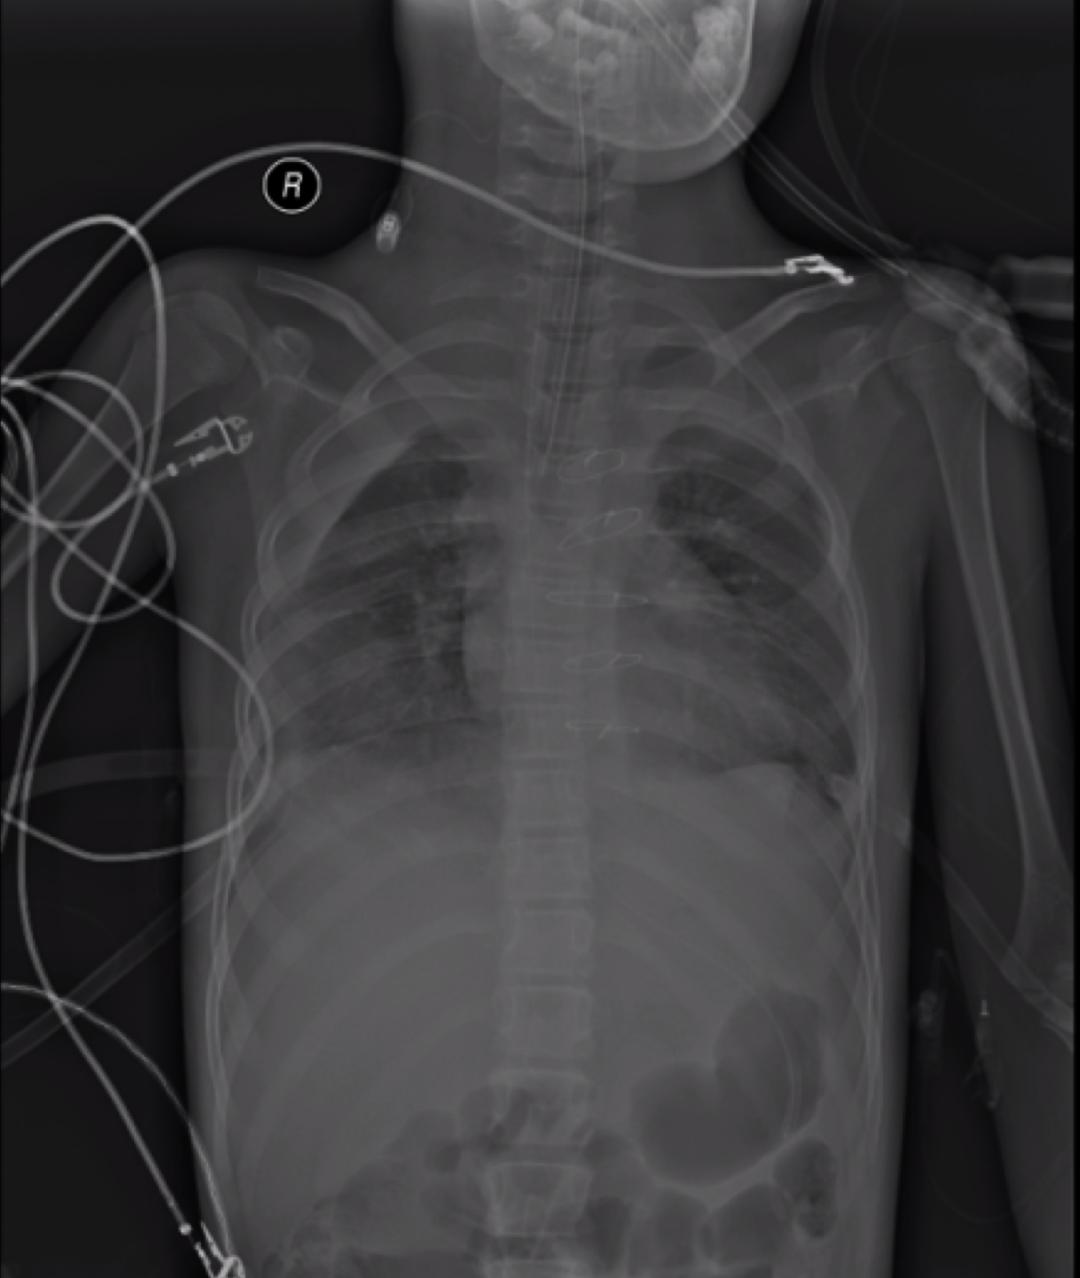

客观资料: 肺部体查(视诊:开胸术后心纵、双侧胸腔闭式引流管,辅助呼吸肌用力明显;触诊:双侧呼吸动度减弱;叩诊:浊音;听诊:双肺呼吸音减弱,可闻及满肺干啰音),呼吸机参数(模式:SIMV+PRVC;VT:170ml;PEEP:5cmH2O;RR:20次/分),生命体征(T:37.1℃;P:110次/分;R:15次/分;BP:127/76mmHg),实验室检查(WBC:13.48×10^9/L;N%:87.1%;L%:7.5%;HGB:111g/L;PLT:17×10^9/L;CRP:8.44mg/l;PCT:9.8ng/ml;TnI:<0.05ng/ml;BNP:866pg/ml;Mb:>500μg/l;CKMB:3.8u/l;FDP:39.49μg/ml;D-二聚体:>5000μg/ml;ALT:89.7u/l;AST:153.4u/l;ALB:34.4g/l;BUN:10.91pg/ml),血气分析(PH:7.403;PCO2:61.9mmHg;PO2:97.1mmHg;HCO3-:35mmol/l;SaO2:97.2%;FiO2:50%;P/F:194.2mmHg)。辅助检查(2019年4月20日床旁胸片:心肺联合移植术后,双肺渗出灶、双侧胸腔积液大致同前;心脏彩超:IVS 6.5mm,LVMi 44.3g/m^2,EF值75%,左心功能大致正常,右室稍显圆隆,收缩、舒张功基本正常,左室壁内膜增厚,约1.5mm;下肢血管彩超:双下肢深静脉血流通畅)。

图:2019.4.20床旁胸片